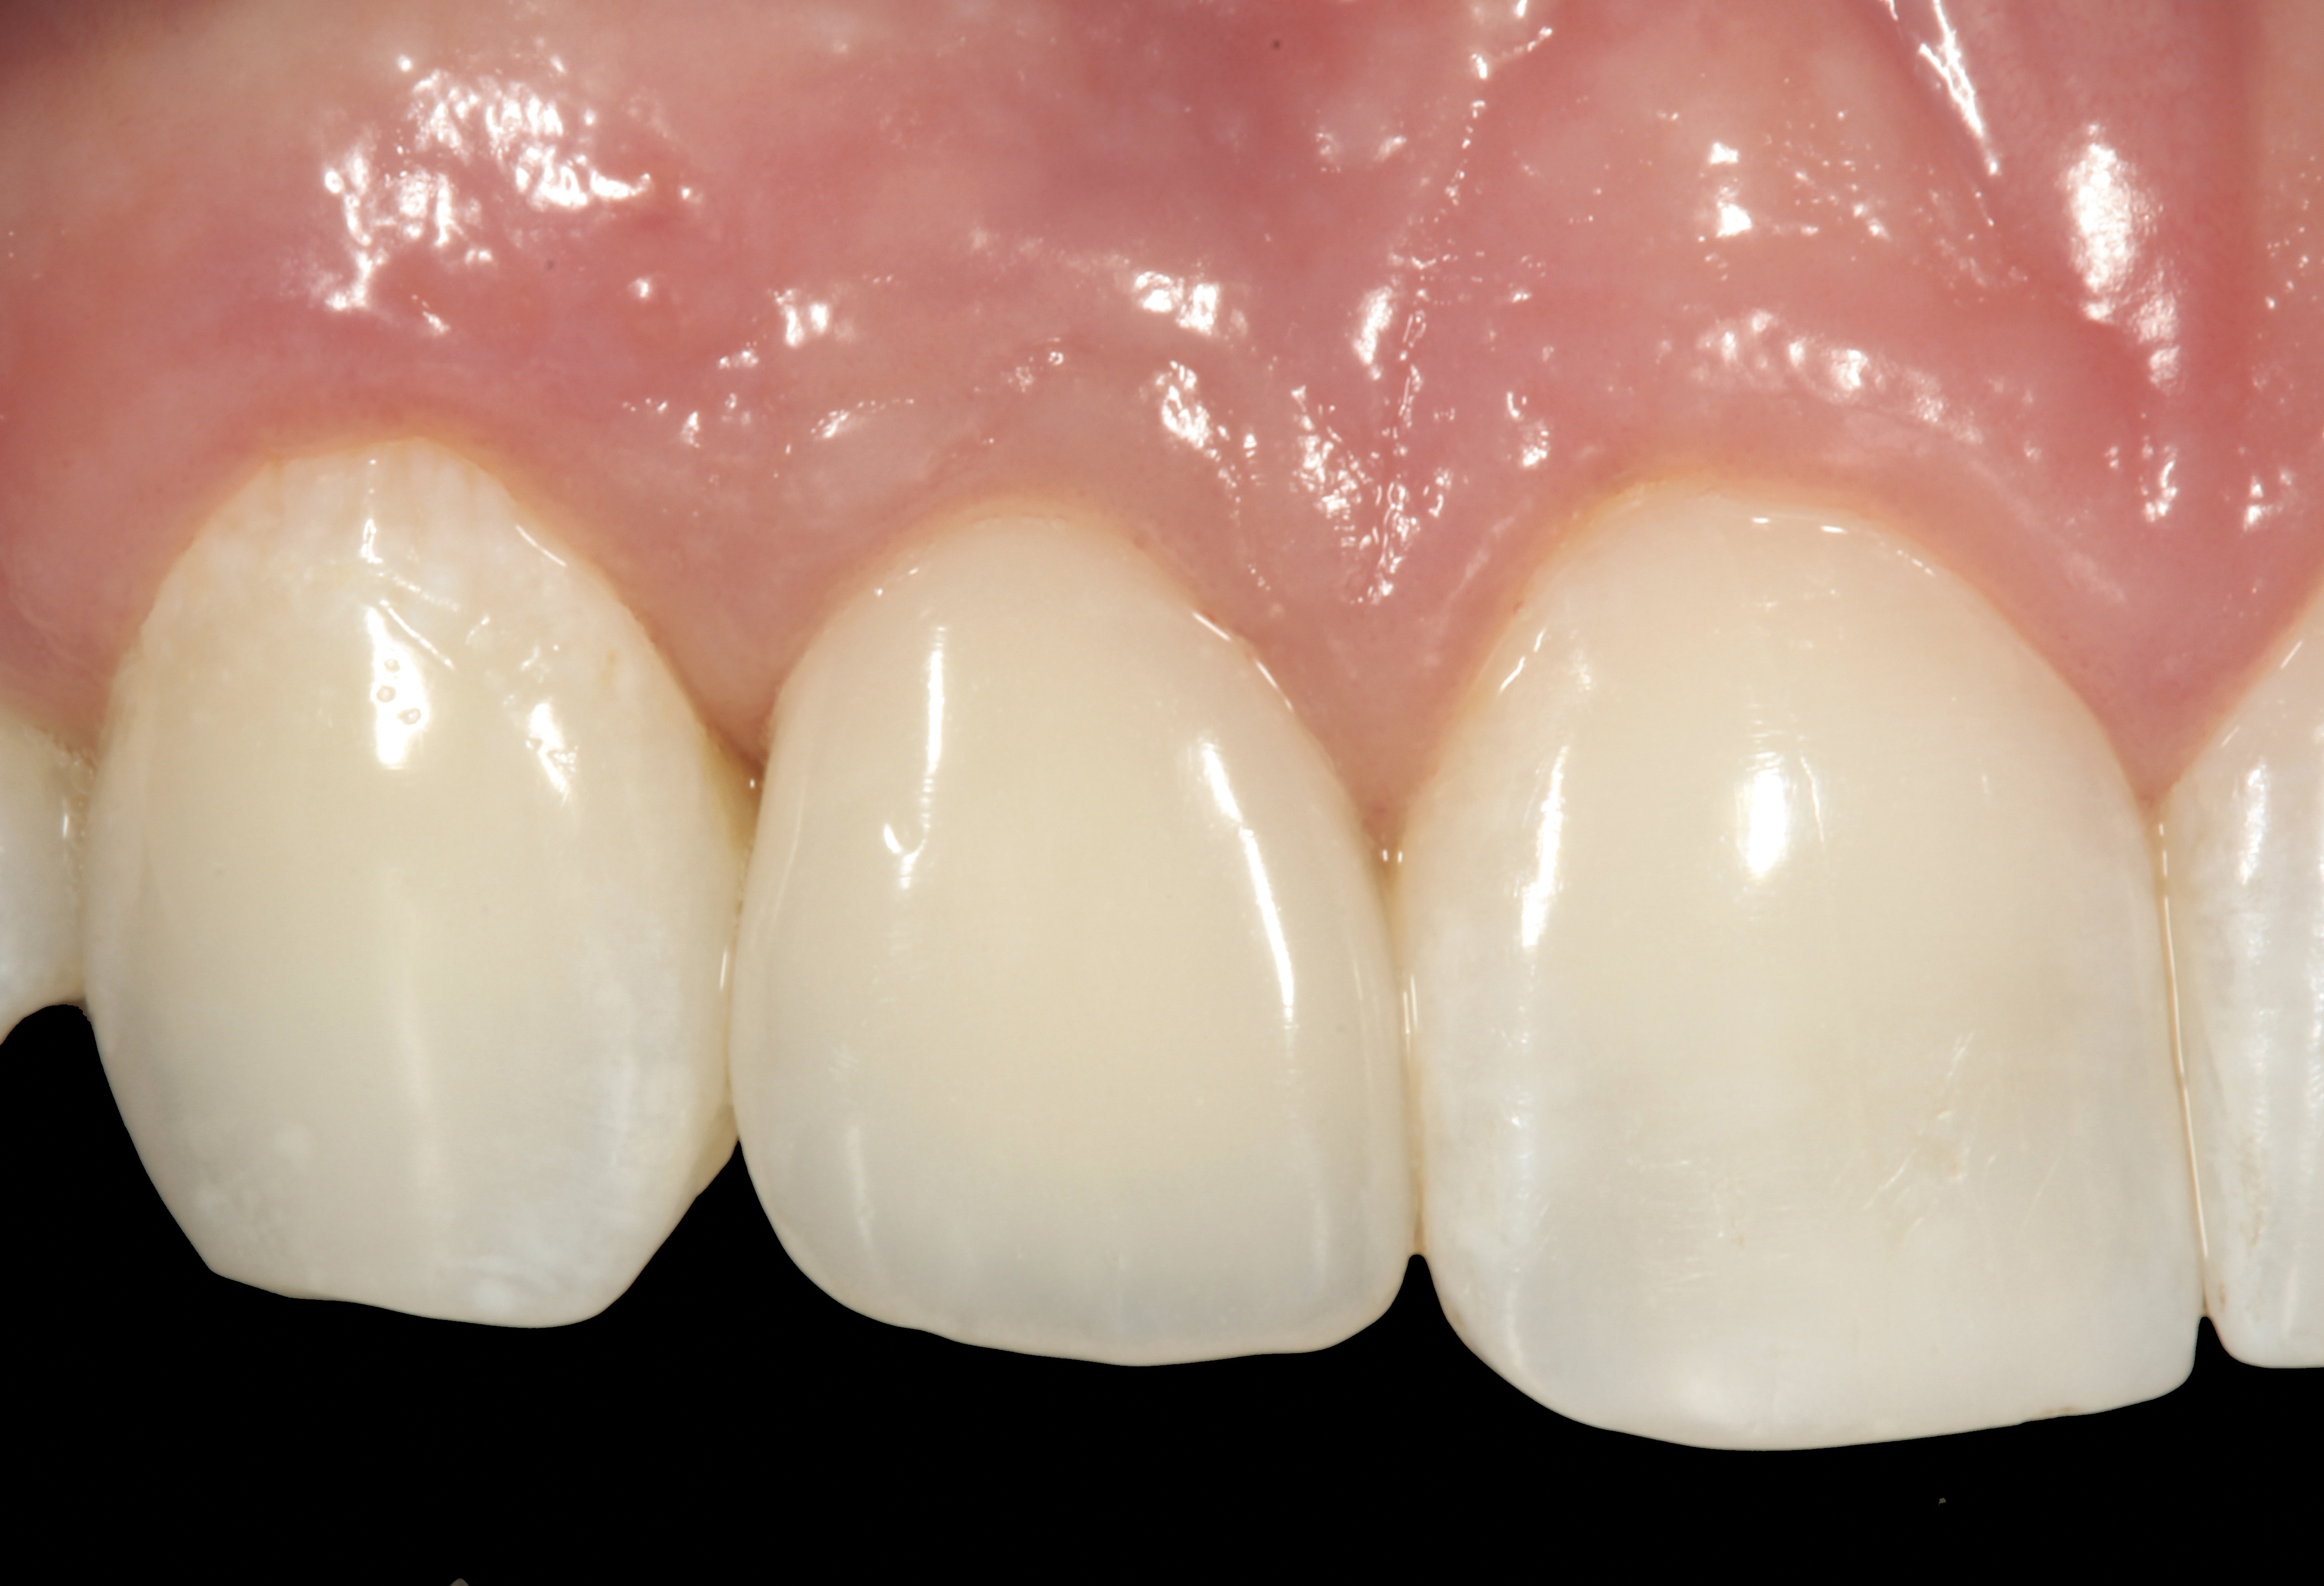

The crown and screw-retained custom abutment were removed, and a surgical cover screw was placed into the implant, thereby allowing spontaneous gingival augmentation in situ (Figure 33 and Figure 34). Note that the lingual aspect of the implant site was significantly more coronal than the labial aspect, which was positive because the defect would be limited to a facial–lingual defect. A fixed RBR bridge was cemented on the adjacent teeth and used as a tooth-supported transitional provisional restoration (Figure 35). A few weeks were allotted to let the soft tissue heal and migrate around the cover screw (Figure 36) to see if there would be complete coverage, thereby allowing a soft-tissue augmentation procedure to be performed with primary flap closure as in clinical scenario No. 2. The major obstacle in achieving a positive tissue response was that the implant depth was also deficient because the implant–abutment connection was at the level of the free gingival margin. It was decided that the best treatment option would be to remove the implant. A high-powered reverse-torque device (Fixture Remover Kit, NeoBiotech, www.neobiotechus.com) was used to remove the implant atraumatically (Figure 38 through Figure 41). The implant socket was allowed to heal for several months not unlike an extracted tooth (Figure 42). A new implant was placed in a better position from both a restorative and esthetic perspective (Figure 43), and after a few months of healing, a new crown was made (Figure 44). A satisfactory functional and esthetic result was achieved (Figure 45 and Figure 46) without employing pink porcelain.

Fig 45. The definitive crown tooth No. 26 seated in place and provisionally cemented. The recession defect was eliminated with the removal and replacement of a new implant in the proper position.

Figure 45